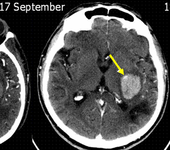

[ISC2017]止血药物或无法阻止脑出血患者的血肿扩大

两项试验的汇总结果显示,虽然CT“点征”能够预测出血扩大、死亡和残疾风险增加,但紧急使用止血药物治疗脑出血患者并没有阻止其扩展或改善其结局。